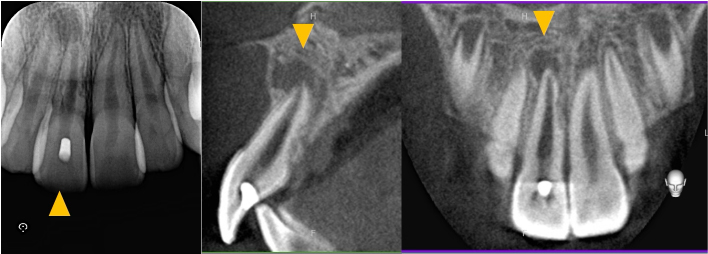

初診来院時の状態では、すでに根の入り口付近に処置が行われている状態でした。患者様によると、腫れた時に少しだけ歯を削ったとのことでしたが、どのような処置が行われていたかは説明を受けていなかったとのことです。

根の先に黒い影(膿・骨の吸収)が認められ、神経の検査では反応がなく、神経が死んでしまっている状態でした。

術後24ヶ月のCT画像にて、根の先の黒い影が消失し、骨が回復していることが確認できます。